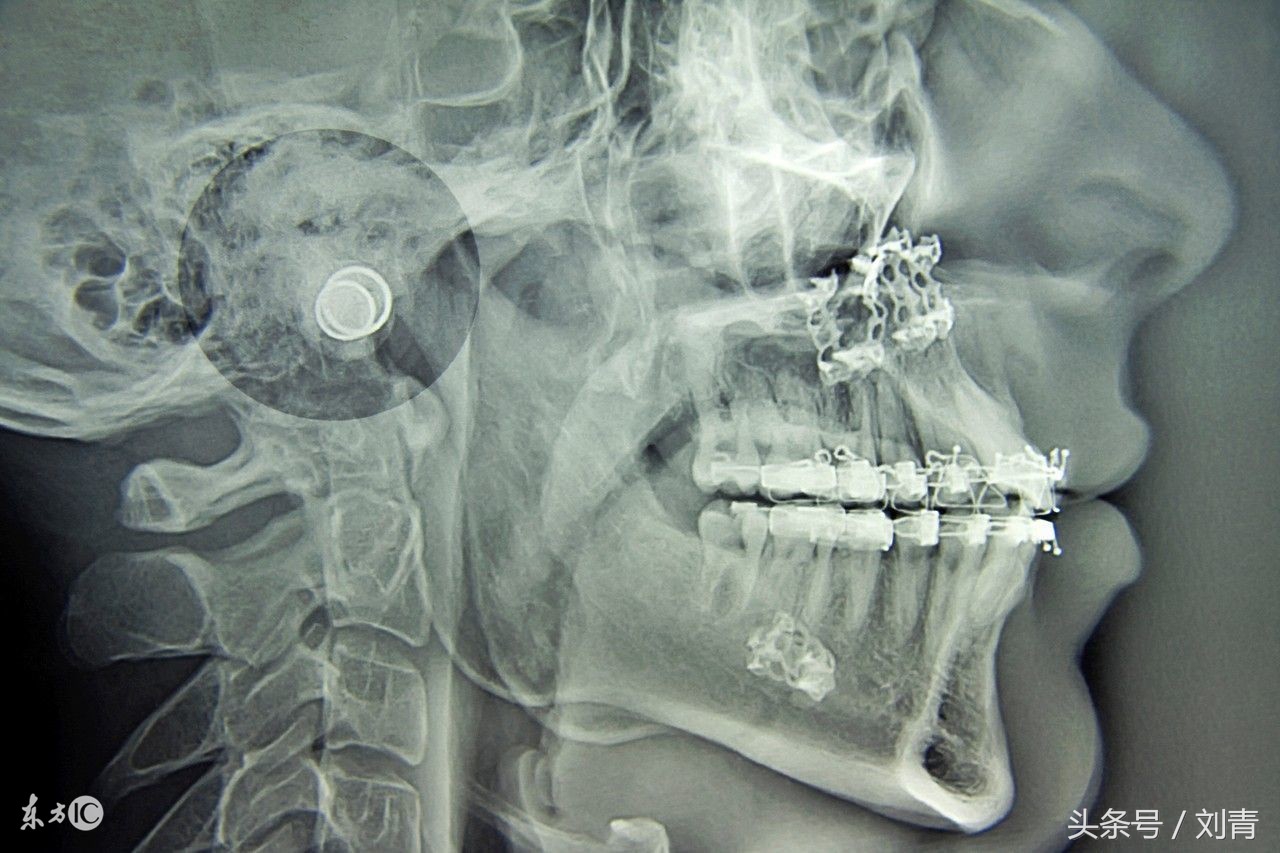

乳牙期反颌危害非常大,若不及时治疗,等到了恒牙期,反颌由牙性反颌变为骨性畸形,整个面形都会发生改变,这时就无法通过移动牙齿来矫正,甚至不能矫正了。

一般来说,4岁~4岁半是“地包天”矫正的最佳时期

很多错颌畸形都是发生在乳牙期,如果不及时治疗,症状会越来越严重。一定要在乳牙期,换牙之前,尽可能把牙齿矫正过来。